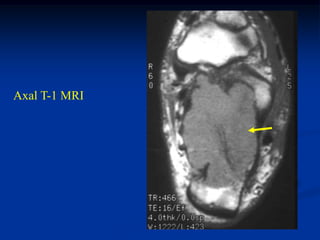

Case #1147             Metastatic Lung

46 year male with central fracture dislocation thru metastatic

lung CA of left peri-acetabular area

Post op appearance following

modified internal hemipelvec-

tomy with cement and pins

with THA